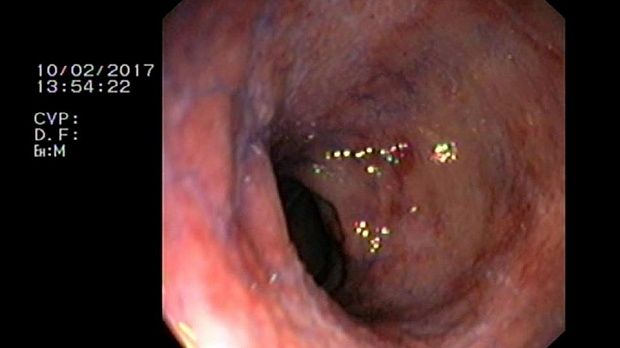

2 мл ( это мин сум, а мы делаем до 10 мл 3% перекись+200 мл физ раствора